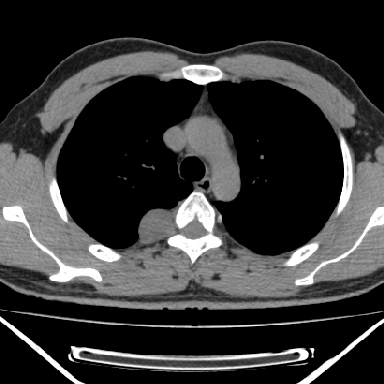

m 30 右胸痛10年

右上后纵隔脊柱旁类圆形肿块,边界光整,与胸腔呈钝角,首先考虑来源于肺外,神经源性肿瘤(神经鞘瘤可能大,神经鞘瘤)

m,30岁,右胸痛10年。

右上后纵隔旁软组织肿块影,与肺界面光滑,与胸壁呈钝角相交,提示肺外病变。位于肋骨下缘,边缘清楚,呈三角样指向与右侧椎间孔,但并示进入椎间孔;与对侧神经根对比,属同一走行方向。

考虑后纵膈良性肿瘤,神经源性肿瘤可能大。

鉴别:胸膜来源肿瘤。影像表现虽有肺外征象,但无胸水等相应佐证;再者,病史前10年,超长,与胸膜肿瘤不太吻合。

建议:再次查体,问清疼痛部位,如为1~2个肋间痛则神经源性肿瘤可能大,如疼痛较弥散,不按肋间分布,则可能为后纵膈其它来源肿瘤。

右上后纵隔脊柱旁类圆形肿块,边界光整,与胸腔呈钝角,首先考虑来源于纵膈,神经源性肿瘤可能大。

右上后纵隔脊柱旁见长椭圆形肿块,边界光整,与胸壁呈钝角。周围骨质未见异常。

考虑、1、后纵隔神经源性肿瘤;

2、不除外单发胸膜间皮瘤。